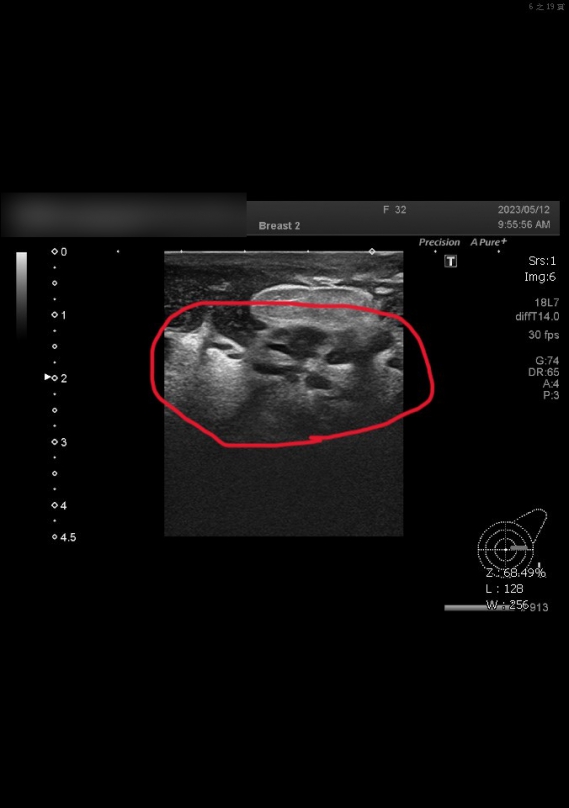

陳國棟醫師說,他給婦人「乳房超音波檢查」,發現已有部分組織壞死,乃將壞死組織手術切除,將膿瘍引流出來,再予抗生素控制,並進行細菌培養,連續兩次檢查都呈陰性,建議切片檢查,驗出「噬酸性結核桿菌」,才知是十分罕見的「乳腺結核病」,乃轉給胸腔內科涂川洲副院長接續治療,陳國棟說.此症狀需服用6個月抗結核病藥物才能根治。